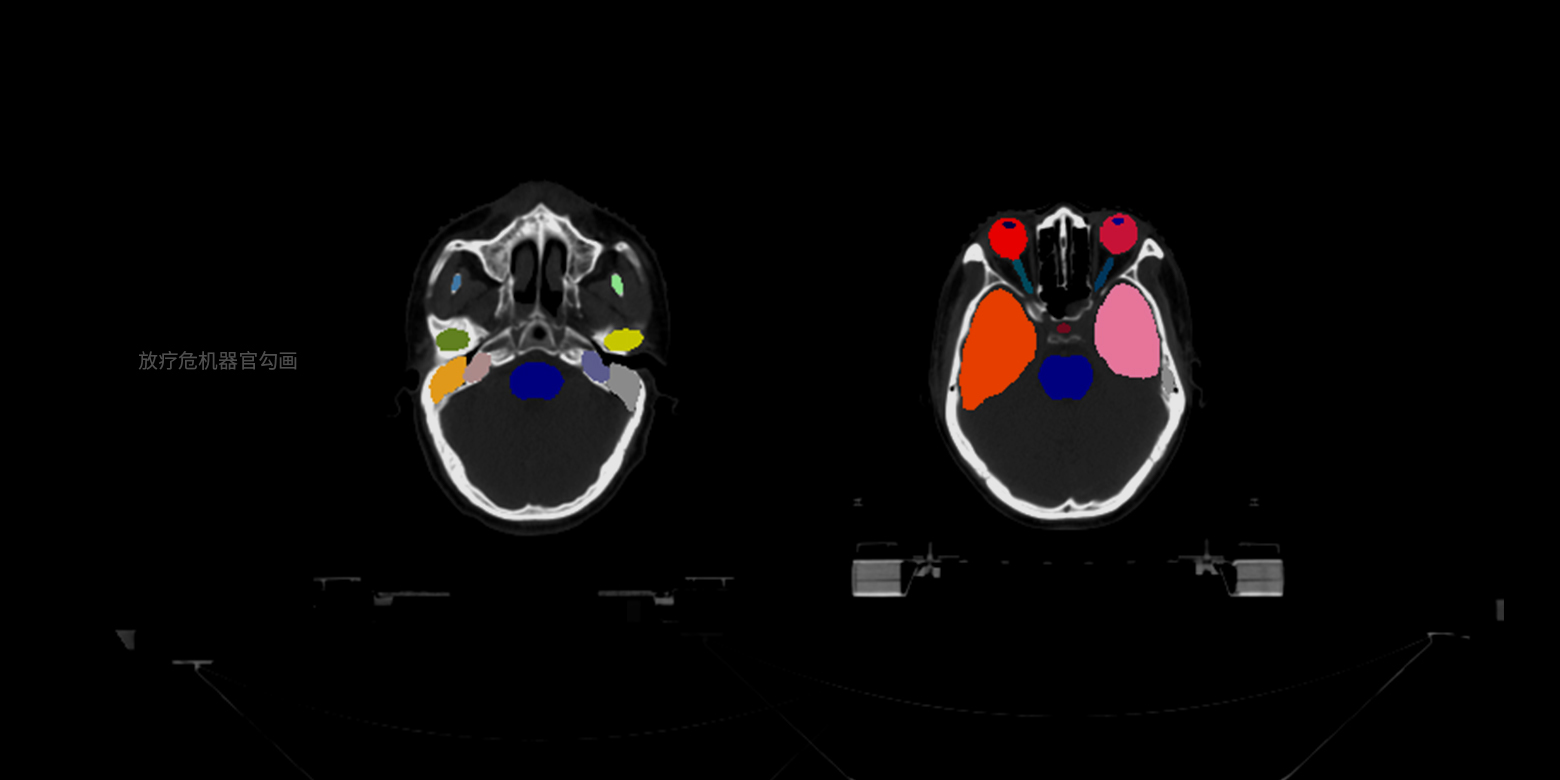

支持基于小样本精细医学数据标注进行训练,实现多种病灶、器官等的像素级精确边界分割,并自动进行关键信息的量化分析,例如放疗靶区勾画、骨盆肿瘤分割等,将医生从耗时耗力的人工手动勾画中解放,满足量化诊断、手术个性化规划等场景的需求。

病灶/部位分割与量化